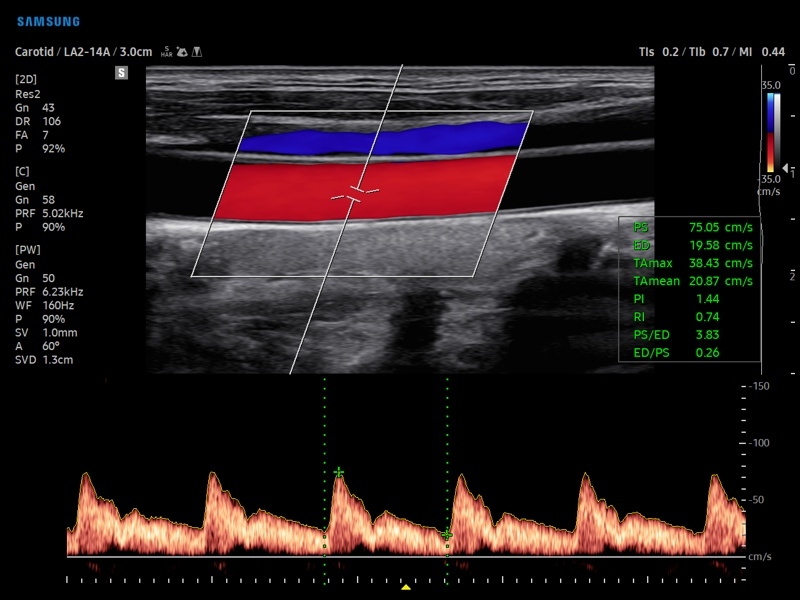

• Ангиология

• Модуль AutoIMT - автоматическое вычисление комплекса интима-медиа общей сонной артерии (Intima Media Thickness). Данная оценка имеет большое значение для ранней диагностики атеросклероза и оценки риска развития инсульта и инфаркта миокарда.

• Модуль 2D Arterial Analysis программа, позволяющая автоматически провести анализ толщины и эластичности стенок разных участков сонной артерии, с выведением результатов в графической форме в движении (кинопетле) аналогично программе Strain для эхокардиографии.

• Сонные артерии:автоматическая, полуавтоматическая, ручная трассировка доплеровского спектра; ПСС, КДС, %СтПлощ, %Ст Диам, площадь сосуда, диаметр сосуда, средняя толщина интимы, объемный кровоток.

• Артерии верхних конечностей:автоматическая, полуавтоматическая, ручная трассировка доплеровского спектра; ПСС, КДС, %СтПлощ, %Ст Диам, площадь сосуда, диаметр сосуда, объемный кровоток.

• Артерии нижних конечностей:автоматическая, полуавтоматическая, ручная трассировка доплеровского спектра; ПСС, КДС, %СтПлощ, %Ст Диам, площадь сосуда, диаметр сосуда, объемный кровоток.